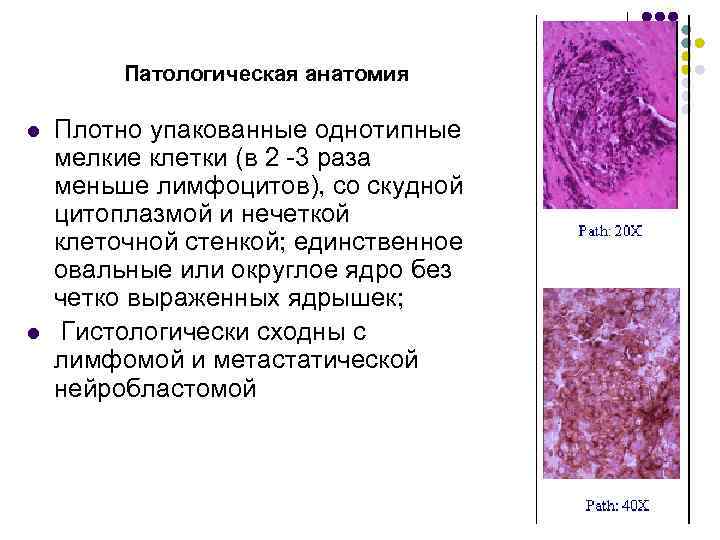

Патологическая анатомия l l Плотно упакованные однотипные мелкие клетки (в 2 -3 раза меньше лимфоцитов), со скудной цитоплазмой и нечеткой клеточной стенкой; единственное овальные или округлое ядро без четко выраженных ядрышек; Гистологически сходны с лимфомой и метастатической нейробластомой

Патологическая анатомия l l Плотно упакованные однотипные мелкие клетки (в 2 -3 раза меньше лимфоцитов), со скудной цитоплазмой и нечеткой клеточной стенкой; единственное овальные или округлое ядро без четко выраженных ядрышек; Гистологически сходны с лимфомой и метастатической нейробластомой